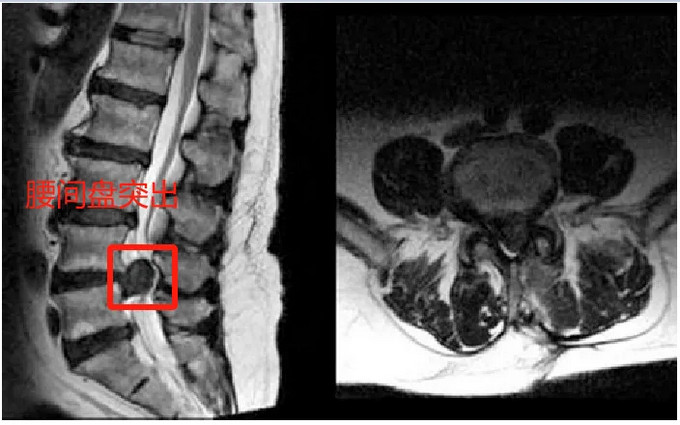

CT和MRI检查是诊断腰椎间盘突出症的主要方法,MRI作为腰椎间盘突出症的首选检查方法,能更准确地提供关于椎间盘变性、硬膜囊受压、脊髓变形、神经根受压、椎间盘突出等多种影像学特征的详细信息。其准确率高于CT,但CT的价格低于MRI,可作为初诊患者的检查方法。同时由于腰椎间盘突出症髓核突出压迫神经易出现表现为神经传导速度减弱的肌电图表现。腰椎间盘突出症患者检验一般炎症指标血沉、CRP正常,HLA-B27阴性。

图片来源于百度